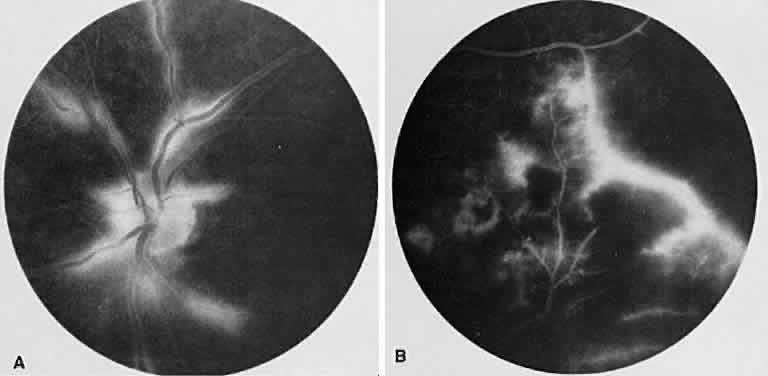

Fig. 18. Acute retinal necrosis. A. Necrotizing retinitis with vitritis, papillitis, intraretinal hemorrhage, and retinal vasculitis. B. Fluorescein angiogram shows areas of hypofluorescence corresponding to choroidal hypoperfusion and intraretinal hemorrhage.

Fluorescein angiography (see Fig. 18B) shows multiple retinal vascular occlusions, particularly arteriolar. In the late phases, the retinal vessels stain, often proximal to the occlusion. Nonoccluded vessels also may show staining.63,64 Late staining of the disc can be seen during the acute phase.64 The differential diagnosis includes herpes zoster retinitis, toxoplasmosis, and Behçet's disease.

Fig. 19. Cytomegalovirus retinitis. A. Fundus photograph of the left posterior pole shows necrotizing retinal changes with vascular sheathing and hemorrhages. B. Angiography shows large areas of hypofluorescence with a central region of multiple focal areas of staining within the lesion. Sheathed vessels stain but do not leak. C. Old cytomegalovirus retinitis. In an area of chronic retinitis, retinal pigment epithelium mottling is seen because of the necrosis.

Fig. 20. Frosted branch angiitis. A. Marked sheathing of retinal vessels with area of active retinitis and intraretinal hemorrhages is seen. B. Leakage of dye from the retinal venules representing retinal periphlebitis. Areas of hypofluorescence also are noted temporally corresponding to the retinitis.

On fluorescein angiography, findings that parallel the clinical appearance can be seen. Fusiform aneurysmal dilations of arteries, arteriole venules, and capillaries as well as capillary microaneurysms can be seen.66 The area of retinitis and necrosis blocks the choroidal fluorescence (see Fig. 19B); however, in the late venous phase, hyperfluorescence of the center lesion can be seen. Branch retinal artery occlusions may be seen.67 In addition, late dye leakage from arteries67 and optic disc occurs.